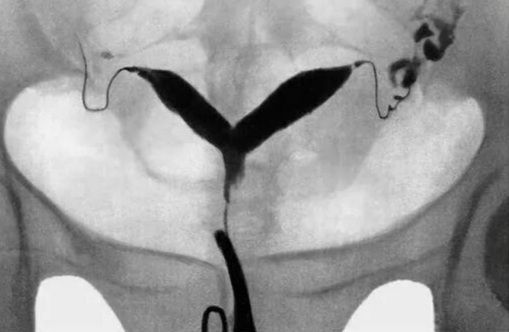

Валентина, нашла картинку в интернете. При двурогой как бы две полости матки. Беременность в одной части.

Наталья, это седловидная больше

Валентина, у меня не седловидная. Два отдельных рога в одном беременность, другой "небеременный" рог продолжил менструировать. При получении квоты и проведении процедуры акцента на патологии никто не делал. Но я думаю многое зависит от репродуктолога. В первой клинике врач меня замучила с этой маткой и пофиг было что элементарно у меня овуляции нет своей